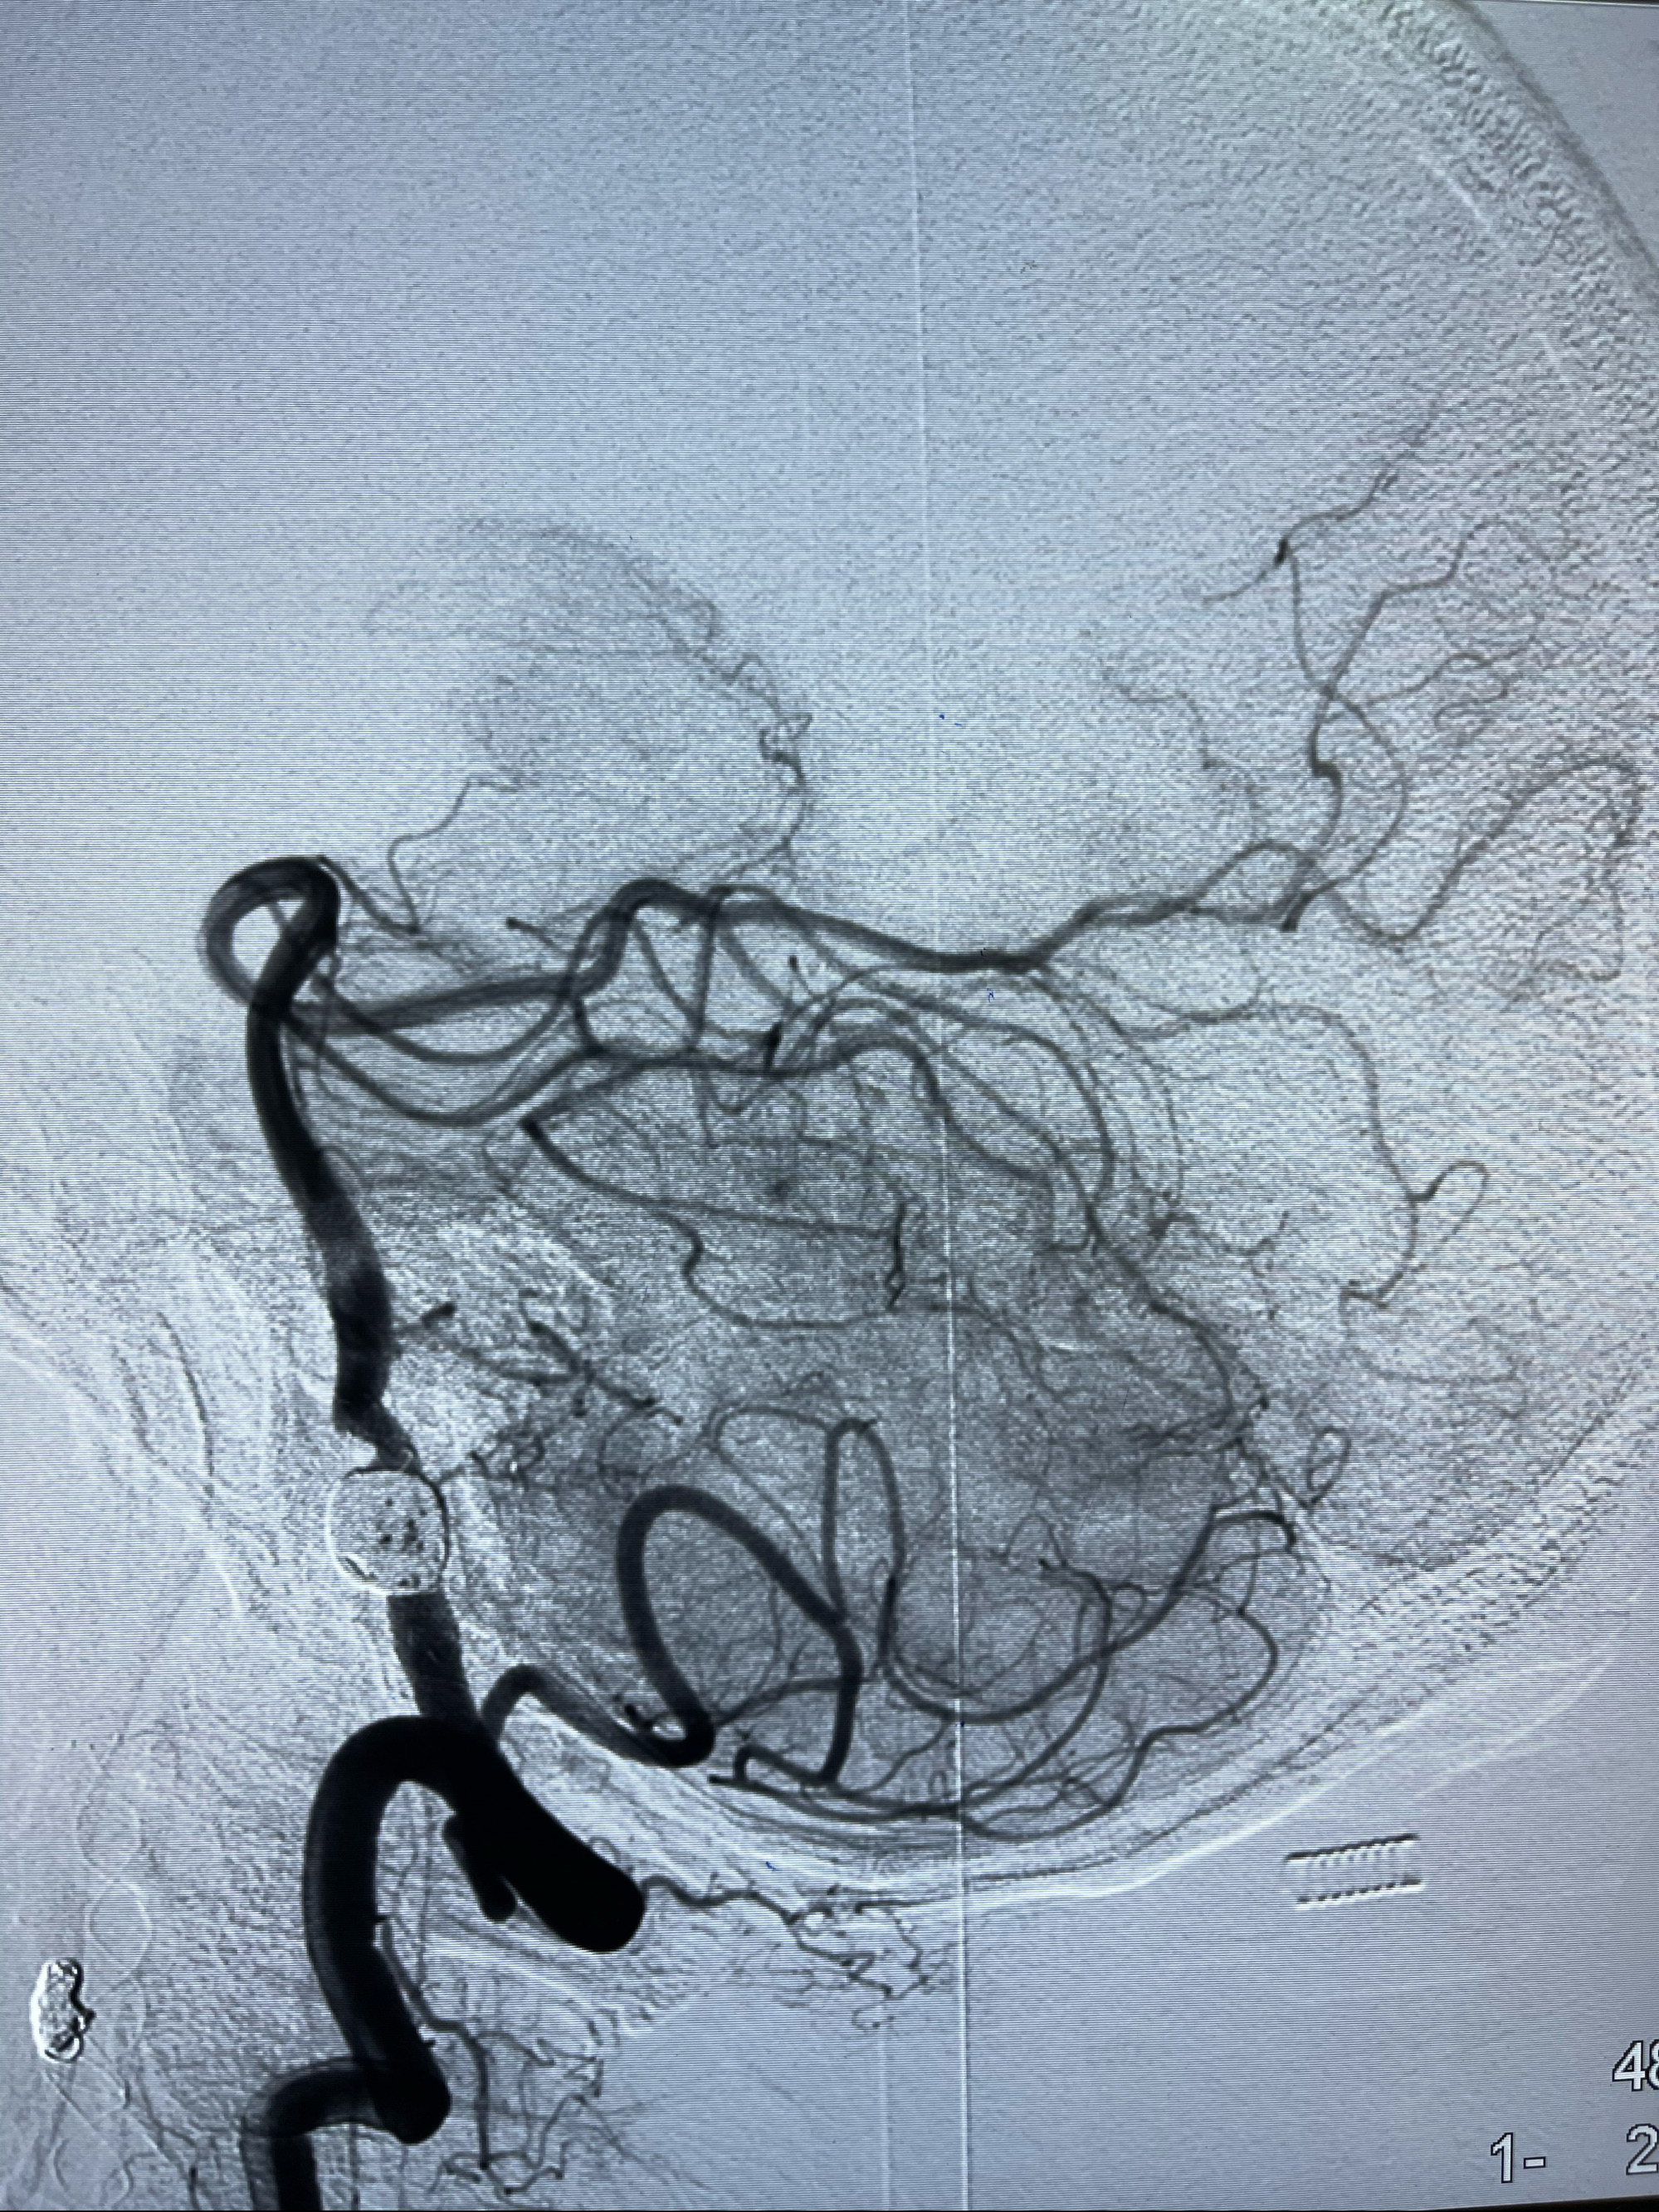

2021-03-08行全脑血管造影

治疗策略:

1.左侧椎动脉夹层动脉瘤密网支架辅助栓塞:

1.右侧颈内动脉夹层动脉瘤Lvis支架辅助;

左侧椎动脉V4夹层动脉瘤多支架辅助栓塞:

1.Enterprise4.0-23mm;

2.Tubridge3.5-30mm密网支架

DA导引导管到位

工作角度造影

Eterprise4.0-23mm支架导管到位

Echelon10 45°角微导管塑形后到位

8mm-40cm微弹簧圈成篮

即刻造影

支架到位

支架释放,透视下